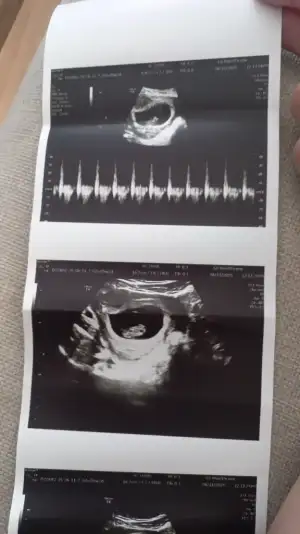

Canim ben en ileriyim galiba 12 haftadayiz ikiliyi bugün verdim normal muayenede ultrasonla burun ve ense kemigine bakıp ölçüsünü söylüyorlar ve sonra ac tok farketmez 1 tüp kan veriyosunuz bu kadar en kapsamlisi 2 li test bundanda kapsamlisi fetal dna testi. Fetal pahali bi test ama 2 li test devlette ücretsiz ikili sıkıntı gorurlerse zaten fetali ozman oneriyorlar